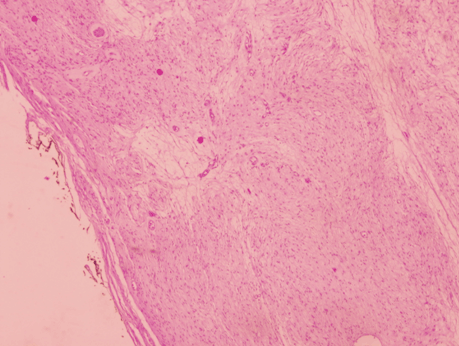

A laparotomy to remove the lesion was scheduled. An encapsulated whitish retroperitoneal tumor attached to right sciatic nerve and easily resectable by blunt maneuvers was identified intraoperatively (Figure 4). The gross specimen was a smooth nodular lesion of 5x4 cm with soft consistency. The greyish cut surface showed the presence of cystic areas. Microscopic examination revealed a well-encapsulated lesion formed by spindle cells with eosinophilic cytoplasm and elongated nuclei without cytologic atypia or pleomorphism arranged in interlacing fascicles (Figure 5) and (Figure 6). Immunohistochemical staining showed diffuse positivity of tumor cells for S-100 protein, but was negative for smooth muscle actin (SMA).

Figure 6: A well-encapsulated lesion without mitoses or atypia (H&E stain, x40).

The definitive diagnosis of schwannoma is based on histopathologic and immunohistochemical findings [8]. Histologically, they are characterized by alternating areas of high and low cellularity, termed Antoni A and B regions. Mitotic figures are rarely observed. Large tumors often show cystic degeneration. Immunohistochemistry is positive for S-100, neuron specific enolasa and vimentin, but negative for SMA. Schwannomas are easily distinguished from leiomyomas or malignant peripheral nerve sheath tumors (NPNSTs). Tumor cells in leiomyomas are negative for S-100, but positive for SMA. NPNSTs have poorly differentiated cells with marked nuclear atypia and frequent mitoses.